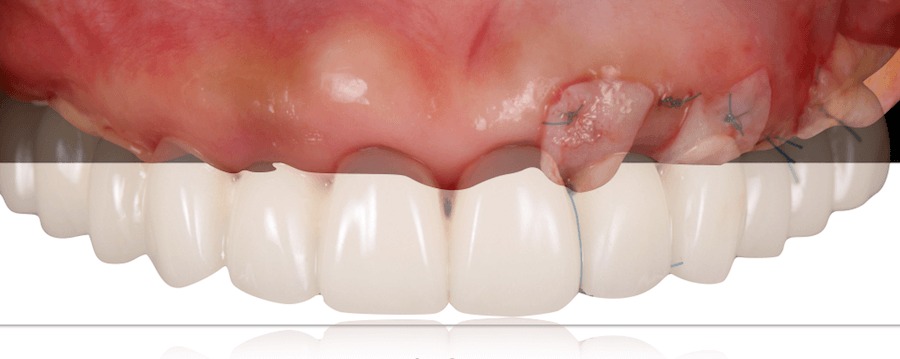

CTGconnective tissue graft

2つ目の仮歯を入れると同時に、軟組織が足りない部分を、結合組織を移植する事で改善する。

最終補綴

2つ目の仮歯で歯肉の形態を整え、審美性、噛み合わせや発音などの機能性、清掃性等に問題が無いことを確認し最終的な補綴物を作る為のステップに移行する。

上顎:セラミックレイヤードフルジルコニアインプラントブリッジ

下顎:前歯部はインビザライン矯正治療で歯並びを改善。臼歯部はインプラント上部にFCZクラウンを使用